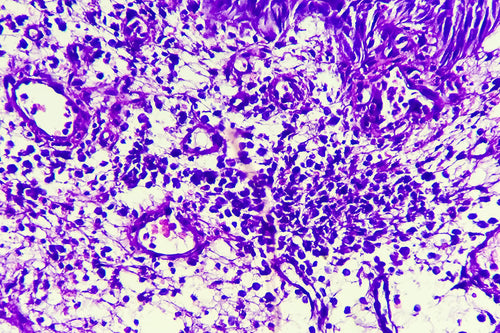

猫とIBD - ステロイドが効かない時に腸内では何が起きているのか?

人間のみならず、近年では猫においてもIBD(もしくはIBD疑い)の診断が増えています。ここでは腸内細菌解析の現場の視点から、猫のIBD、そしてステロイドが効かなくなる背景について記載します。